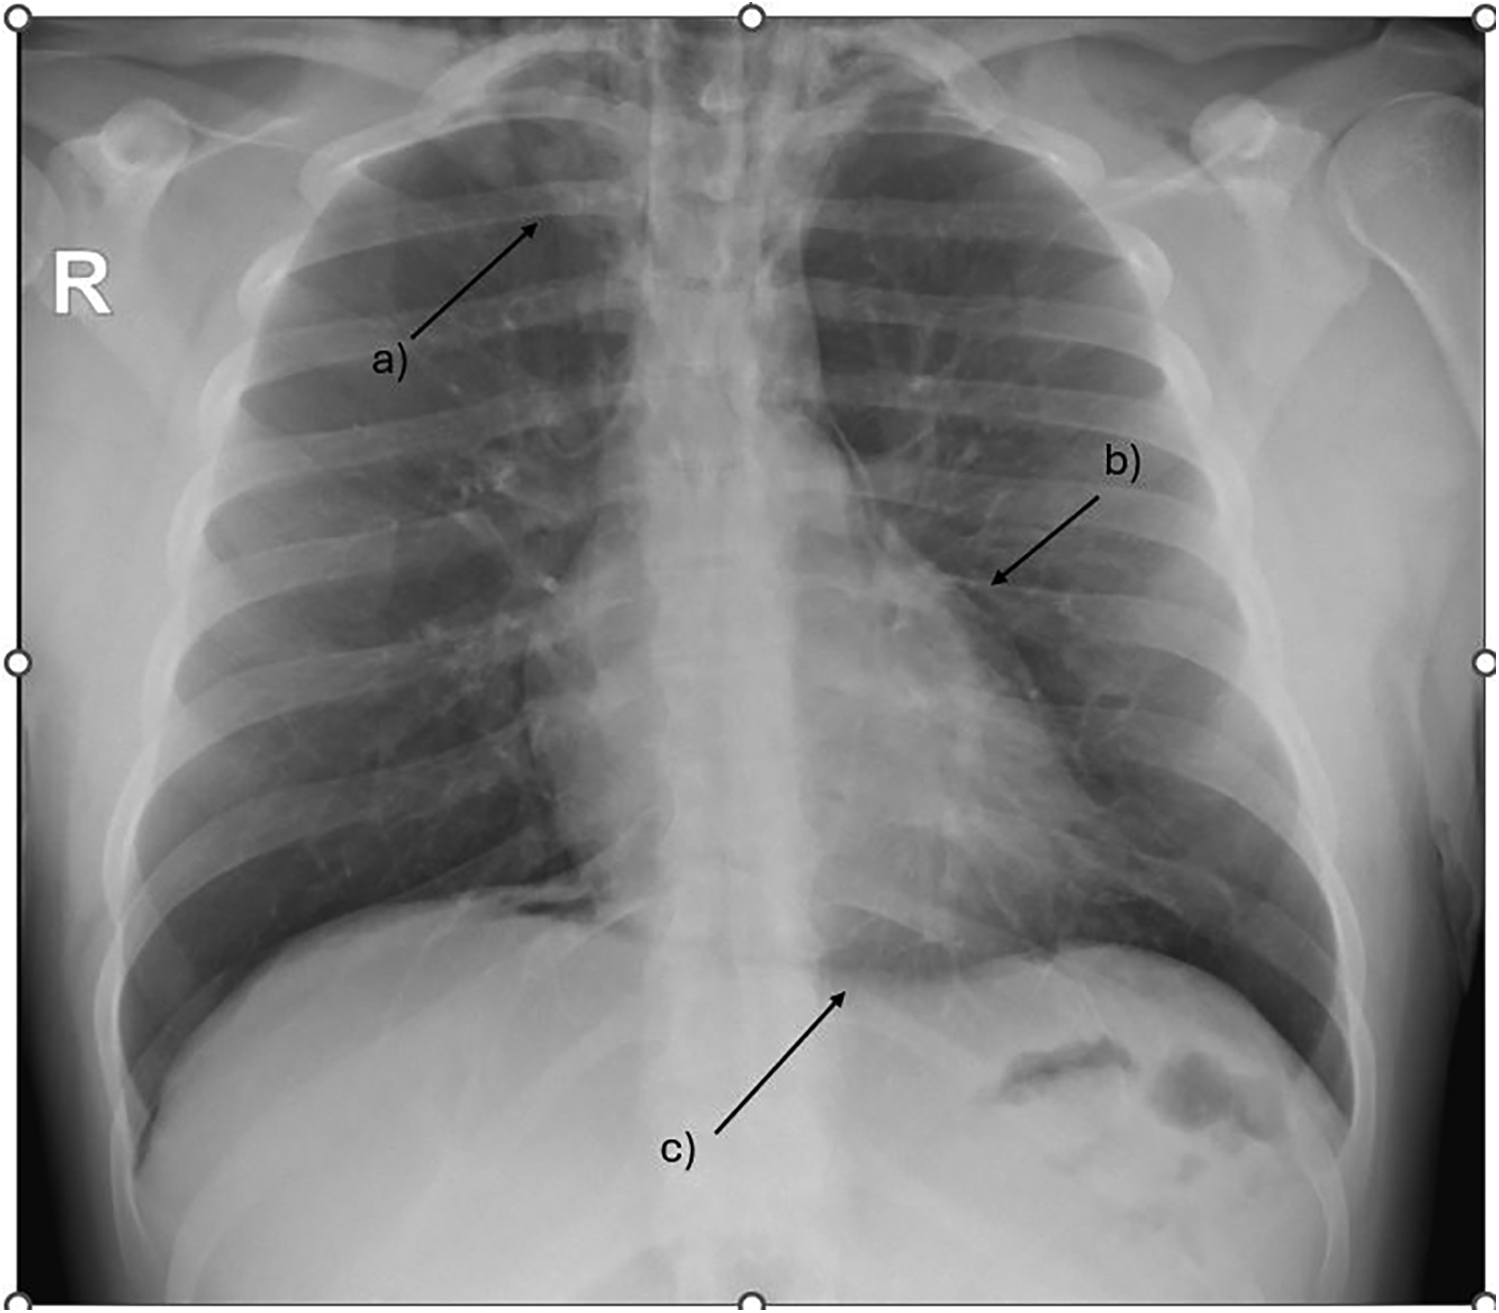

During acute coronary syndrome (ACS) exclusion workouts, transthoracic echocardiography images were very difficult to obtain, as hyperechoic moving artifacts were interfering with the ultrasound probe. Immediate chest x-ray showed massive pneumomediastinum (Figure 1). A subsequent CT scan confirmed the massive pneumomediastinum (Figure 2) and revealed the presence of an acute bilateral pulmonary embolism (Figure 3). Laboratory tests showed elevated D-Dimer levels (2,515 ng/mL), polycythaemia (hemoglobin 18.9 g/dL, haematocrit 55.5%), and slightly elevated creatinine (1.48 mg/dL, creatinine clearance 49 mL/min) with mild hypoalbuminemia (3.2 g/dL).

Figure 1

Chest x-ray showing massive pneumomediastinum tracking up to the base of the neck. (a) subcutaneous emphysema (b) extra pleural air sign (c) the continuous diaphragm sign.